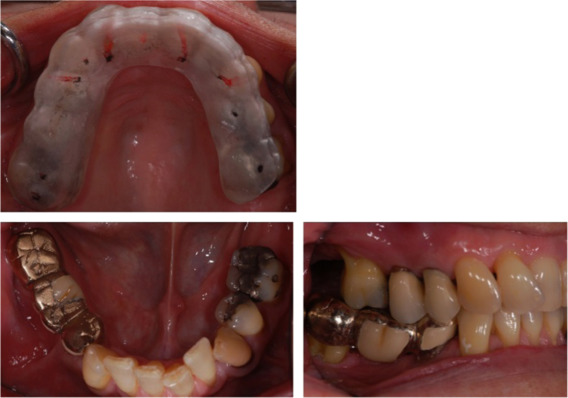

A 58 year old woman was referred by her general dental practitioner for the provision of restorative care of a failing two unit fixed dental prosthesis in the fourth quadrant (Fig. 1 ).

Fig. 1

Fig. 1.

Pre-operative dental panoramic tomograph and right side lateral and mandibular occlusal views.

The fixed dental prosthesis restoration (teeth 46–45) was considered terminal and extraction was planned of the 46 abutment tooth. The adjacent teeth 47 and 44 were heavily restored and single cast restorations were considered, however the patient wished to replace the presenting 45 space. A new three unit conventional fixed dental prosthesis restoration was planned for teeth 47–44. It was felt that splinting the 47 and 44 would share the occlusal load imparted on that quadrant without affecting their prognosis. Radiographic generalised periodontal bone loss was evident (Fig. 1 ) but no clinical mobility was detected around the proposed abutment teeth. The generalised periodontal probing profile did not reveal any pockets over 3 mm and no furcation defect was detected on probing the 47. The patient׳s periodontal condition was stable as had been receiving regular periodontal maintenance at a specialist treatment centre.